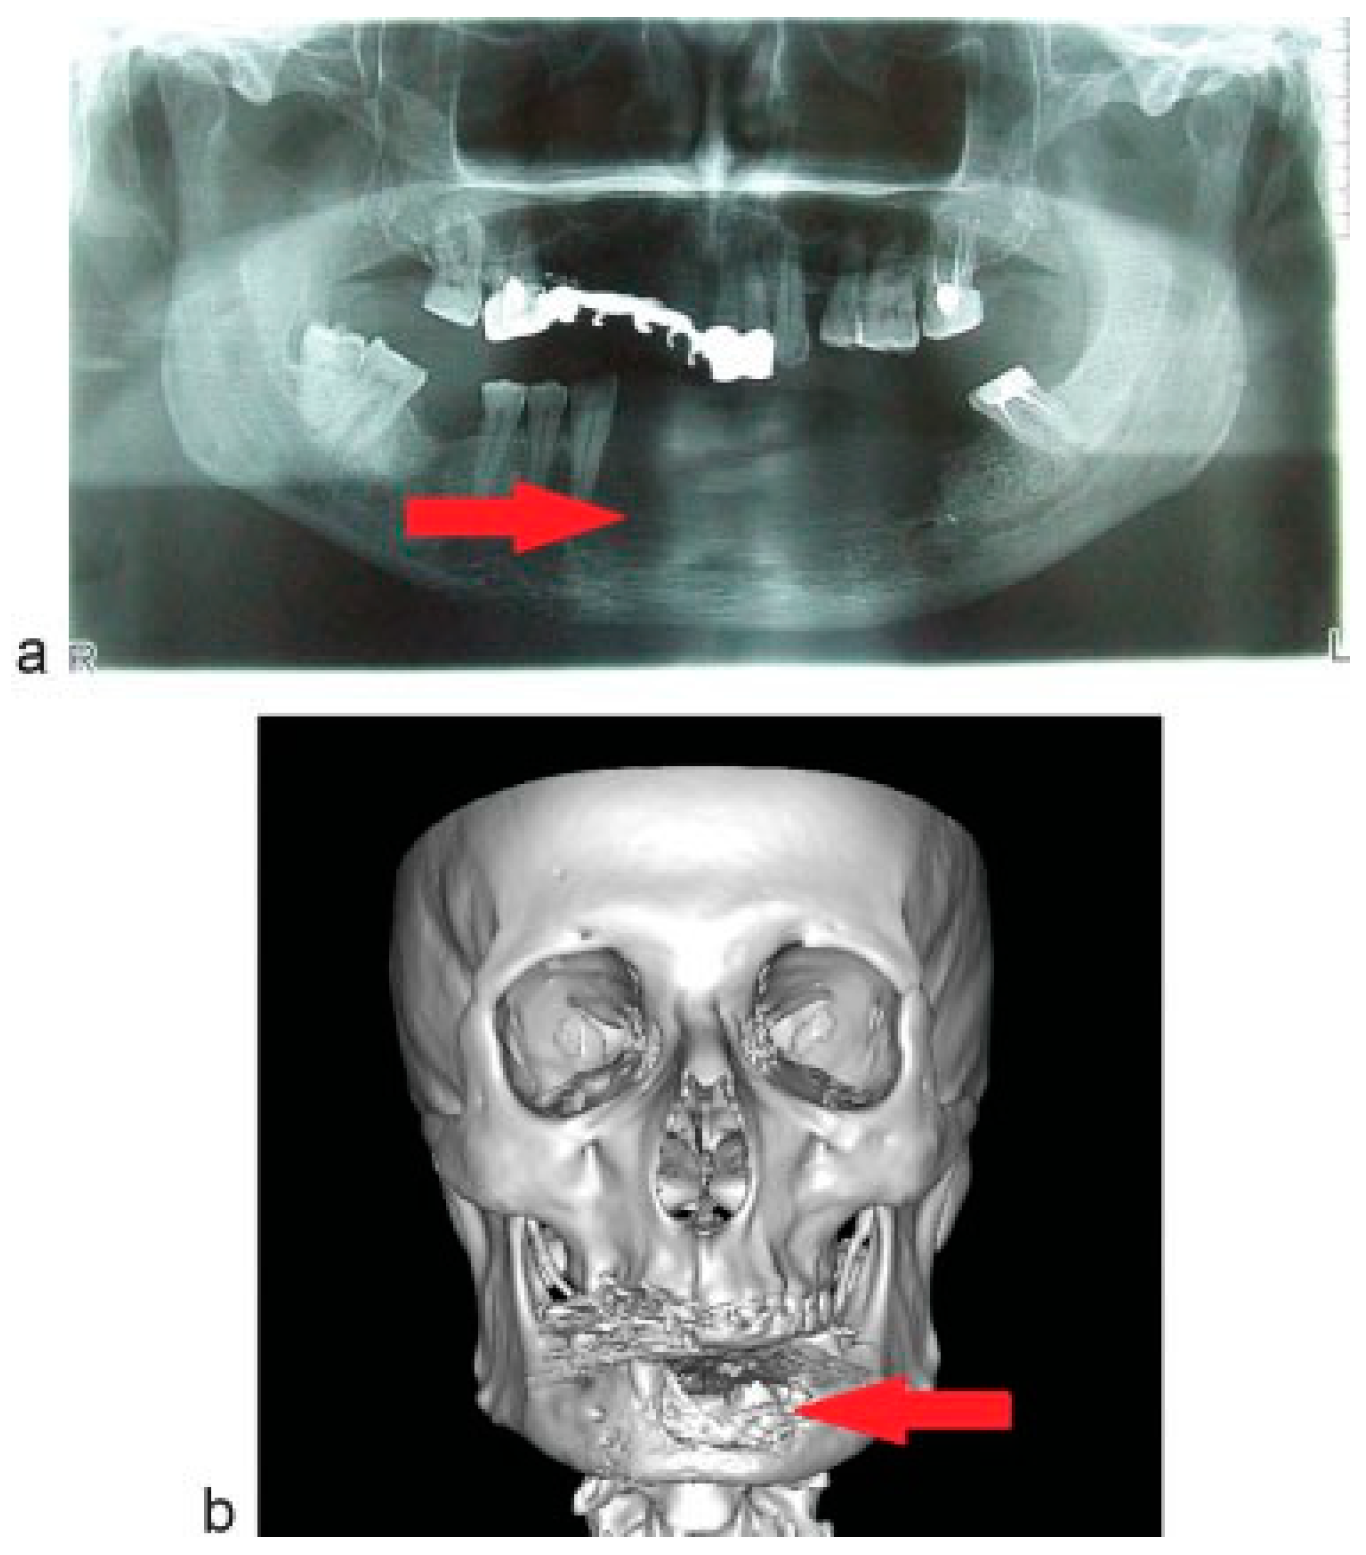

Case Report

A 56-year-old man presents with complains of lesion in the symphysis of the mandible. Upon anamnesis, first signs of disease noted a year ago after the extraction of the 31st and 32th teeth. The tumor developed within the socket after tooth extraction. The tumor was “excochleated”, and a year later the tumor recurred. Clinically, the tumor was found in the region of alveolar process limited by premolars and spreading to oral mucosa of the floor of the mouth (Figure 1a,b). Orthopantomogram (OPG) and computed tomographic (CT) scan showed the area of bone erosion (Figure 2a,b).

Figure 2. (a) Preoperative radiological picture: OPG. (b) Preoperative radiological picture: 3D CT scan. The area of bone destruction (arrow).